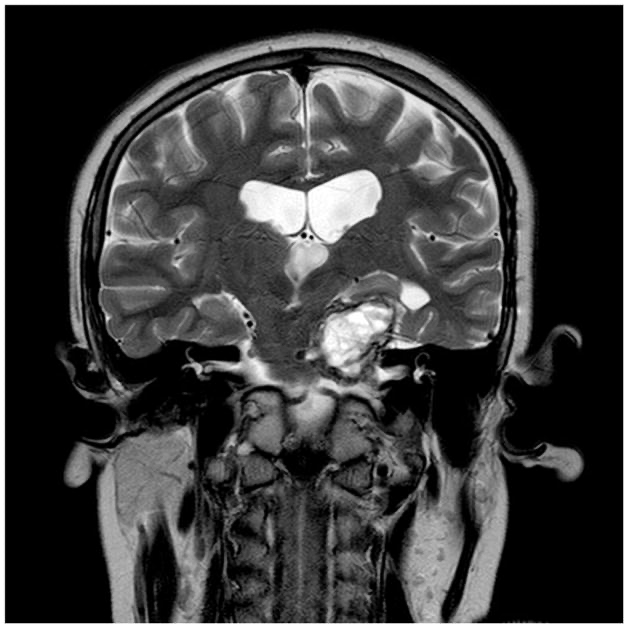

囊性颅咽管瘤用Ommaya储液囊保守治疗,上图为置入Ommaya储液囊之前

囊性颅咽管瘤用Ommaya储液囊保守治疗,上图为置入Ommaya储液囊之后以及反复拍打之后,囊肿大小明显减少